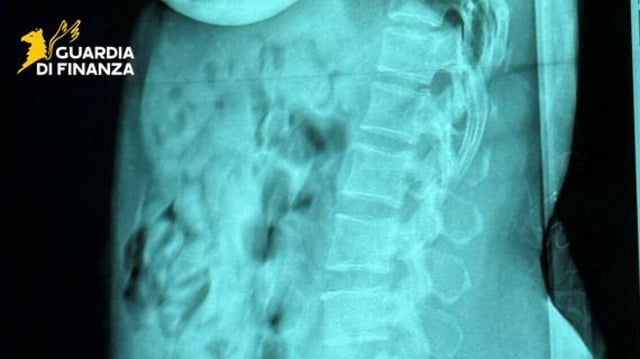

A Belgian customs tip triggered checks that led to hospital scans confirming about 1.4 kilograms of heroin.

• Radiology at Bergamo’s Papa Giovanni XXIII Hospital showed 120 rigid, tape-wrapped packets inside her body, which were later expelled, analyzed and found to contain 1,393 grams of heroin.